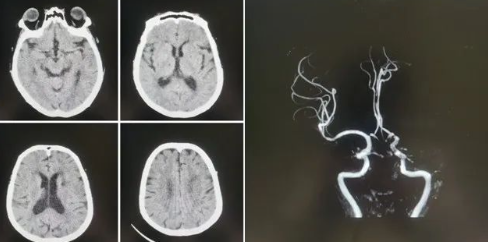

77歲的張阿姨(化名)家住公主嶺市劉房子街道,在活動(dòng)中突發(fā)意識(shí)不清、言語不能,家屬在發(fā)病后1小時(shí)內(nèi)緊急將患者送至我院急診。急診科醫(yī)生第一時(shí)間查看病人,患者高齡,進(jìn)展性意識(shí)不清、言語不能,雙眼向左側(cè)凝視,壓眶疼痛刺激下左側(cè)肢體可抬起,右側(cè)肢體肌力0級(jí),緊急啟動(dòng)卒中救治綠色通道,立即進(jìn)行頭CT檢查,排除出血后,考慮急性缺血性腦卒中,因患者發(fā)病時(shí)間短,緊急聯(lián)系卒中中心團(tuán)隊(duì),國(guó)文醫(yī)院卒中中心丁金明主任第一時(shí)間聯(lián)系影像科進(jìn)行了頭部核磁血管檢查,確診為左側(cè)大腦中動(dòng)脈急性閉塞。

緊急啟動(dòng)導(dǎo)管室、麻醉科,在導(dǎo)管室、麻醉科人員的配合下在全麻下進(jìn)行了腦血管造影術(shù),造影顯示:III型弓,左側(cè)大腦中動(dòng)脈M1段閉塞,余血管未見異常,立即進(jìn)行左側(cè)大腦中動(dòng)脈閉塞取栓術(shù),因?yàn)榛颊逫II型弓,動(dòng)脈硬化重,血管迂曲嚴(yán)重,在泥鰍導(dǎo)絲指引下,利用同軸技術(shù)(6F長(zhǎng)鞘+5F多功能造影管)反復(fù)嘗試超選左側(cè)頸總動(dòng)脈失敗。

在神經(jīng)介入團(tuán)隊(duì)丁金明主任、朱洪波副主任共同努力下,通過交換技術(shù)成功超遠(yuǎn)目標(biāo)血管,釋放取栓支架,通過取栓支架取出一團(tuán)塊狀血栓,成功開通左側(cè)大腦中動(dòng)脈血流,挽救了患者的生命,術(shù)后頭CT檢查未見出血,轉(zhuǎn)入重癥監(jiān)護(hù)病房進(jìn)一步治療。

神經(jīng)介入團(tuán)隊(duì)丁金明主任表示:機(jī)械取栓術(shù)是急性腦梗死治療的終極武器,但需要嚴(yán)格把握時(shí)間窗與適應(yīng)癥。此例手術(shù)的成功得益于三大要素:1、患者及時(shí)送醫(yī)及我院卒中救治綠色通道的高效性。2、多學(xué)科高效協(xié)作:神經(jīng)介入科聯(lián)合急診科、影像科、麻醉科等多團(tuán)隊(duì)無縫銜接,實(shí)現(xiàn)診斷-決策-手術(shù)一體化救治。3、團(tuán)隊(duì)對(duì)手術(shù)細(xì)節(jié)的精準(zhǔn)把控和術(shù)中高清影像導(dǎo)航,成功清除顱內(nèi)大血管血栓,術(shù)后血流恢復(fù)達(dá)‘TICI 3級(jí)’(完全再通),未來我們將進(jìn)一步優(yōu)化救治流程,讓更多卒中患者重獲新生。